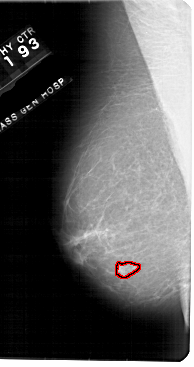

FILE: A_1948_1.LEFT_CC.OVERLAY

TOTAL_ABNORMALITIES 1

ABNORMALITY 1

LESION_TYPE MASS SHAPE IRREGULAR MARGINS ILL_DEFINED

ASSESSMENT 4

SUBTLETY 3

PATHOLOGY BENIGN

TOTAL_OUTLINES 1

BOUNDARY